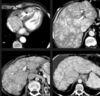

As lesões focais hepáticas na imagem são suspeitas para metástases.

Sequências GRE em fase/fora de fase.

Falso.

As lesões na imagem correspondem a esteatose multifocal/multinodular.